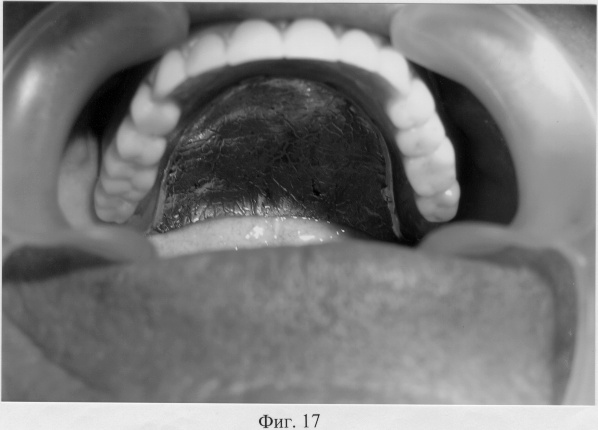

На фиг.17 – полный съемный зубной протез верхней челюсти в полости рта больного Т. при открытом рте.